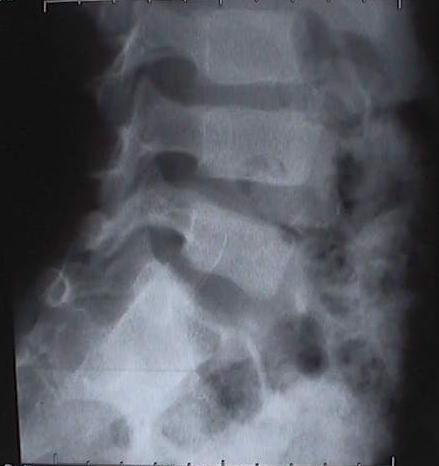

Quand ces anomalies se présentent à un très jeune âge et entraîne une scoliose, il n’y a parfois que la chirurgie qui permet de trouver une solution. Nous vous proposons un cas très particulier d’une hémi-vertèbre droite semi-segmentée L5 fusionnée en S1 avec lyse isthmique et densification des bords L4 gauche chez un enfant de 7 ans : L’histoire de O’Malay (né en 1995)O’Malay, de dos le 13 décembre 2000 La raison pour laquelle la maman de O’Malay amène son fils chez l’ostéopathe, c’est parce qu’il se tient mal ! Dès le déshabillage, le simple fait de mettre O’Malay devant la glace quadrillée montre qu’il y a effectivement un quelque chose d’anormal. La photo est parlante par elle-même. Il est proposé à la maman de faire une radiographie de l’ensemble de la colonne (full spine) et de la région lombaire, face et profil. C’était le 13 décembre 2000. En voici les résultats.Radio de profil : Hémi-vertèbre droite de L5Radio de face de L 5Radio de profil de L 5Radio du bassin de faceRadio de trois quarts : droit & gauche Un scanner est effectué en 2001, dont la technique comporte une acquisition hélicoïdale de 3 mm avec des reconstructions 2 D et 3 D.Scanner avec acquisition hélicoïdale La conclusion est nette : « On retrouve l’hémi-vertèbre droite semi-segmentée L5 fusionnée en S1. II s’y associe une lyse isthmique avec densification des bords L4 gauche (vertèbre sus jacente) ».Scanner avec reconstruction en 3 DDécision chirurgicale Une décision chirurgicale est prise avec comme indication : « résection de l’hémivertébre par doubles voies d’abord pour éviter le déséquilibre progressif qui va s’accentuer petit à petit avec la croissance ». L’intervention chirurgicale se passe très bien. La voie d’abord antérieure est privilégiée avec dissection du muscle psoas droit et résection triangulaire de l’hémi-vertèbre.La voie d’abord postérieur est ensuite réalisée : ablation complète de l’hémi-vertèbre et mise en place d’un matériel avec crochet sur le trou sacré de S2 et sur la lame de L4. Un greffon osseux est mis en place aussi bien en avant qu’en arrière.Un corset de maintien lombaire sera porté pendant 4 mois. La mise debout est progressive. Un contrôle radiologique est effectué pour vérifier la position de la colonne vertébrale, celle du matériel et du greffon.Contrôle radiologique postopératoireMise en route… La mise en position debout ne se fait pas comme prévu : Une sciatalgie droite est diagnostiquée avec « douleurs suspendues au niveau du creux poplité, variable dans sa symptomatologie au cours des journées d’hospitalisation ».La douleur disparaît en position allongée et revient dès la reprise de la marche.Un IRM est pratiqué sans résultat. Le retour à la maison est effectif 10 jours après l’intervention avec une prescription d’antalgiques. Dès le lendemain, les douleurs dans le membre inférieur s’aggravent en position debout au point que la marche est impossible. La maman prend sur elle d’aller revoir l’ostéopathe. En fait, O’Malay souffre d’une psoïte aiguë, avec signe du héron manifeste et une perte complète de confiance dans son membre inférieur droit. Un traitement ostéopathique tissulaire est entrepris au niveau de la cicatrice antérieure, ce qui permet de soulager la douleur de la cuisse.La douleur de type sciatalgie, diagnostiquée à l’hôpital est provoquée par une hyper-contracture des ischio-jambiers qui servent à maintenir l’enfant debout, genou plié.Un ré-apprentissage de la marche se fait progressivement dans la foulée à genoux de manière ludique.Progressivement, O’Malay passe des pleurs au sourire puis, tout à coup, ce sont des éclats de rire. La partie semble gagnée. La maman appelle le lendemain au téléphone pour annoncer triomphalement que son fils est debout et marche normalement.Cette photo a été prise le 14 octobre 2002Chapeau au médecin orthopédiste ! En consultant l’ensemble du dossier de cet enfant, né en 1995, on ne peut que dire « chapeau » au chirurgien orthopédiste qui a pris la responsabilité d’opérer.